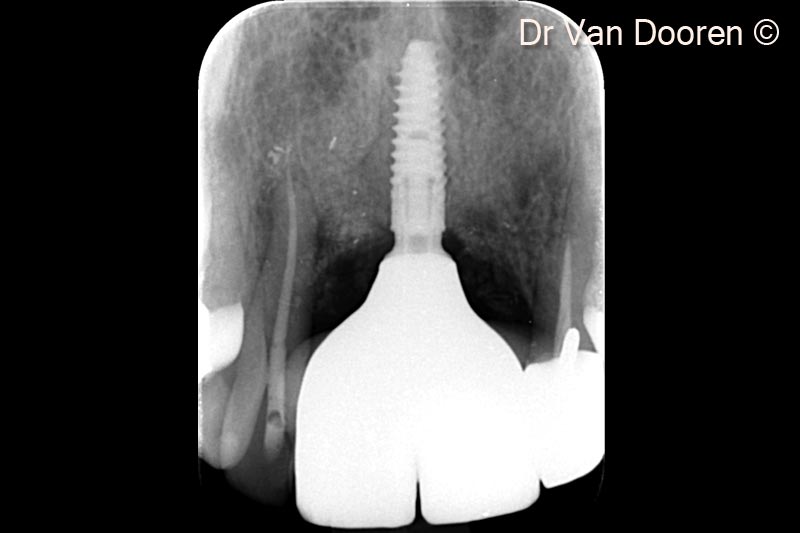

Tình trạng tiêu xương đáng kể xung quanh các implant hiện có và phía gần răng cửa bên: hai implant đã được tháo bỏ.

Tình trạng tiêu xương đáng kể xung quanh các implant hiện có và phía gần răng cửa bên: hai implant đã được tháo bỏ